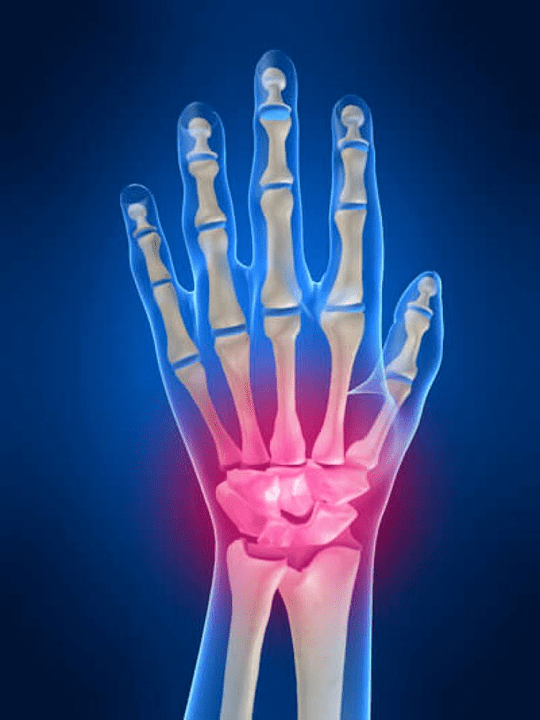

Joint painThe fingers are an essential sign of any joint pathology where the structural components of these joints are damaged.First, pain in these joint areas may be associated with various autoimmune diseases (Red luster throughout the body, rheumatoid arthritis, psoriatic arthritis, etc.) Among them, immune factors will damage their own joint tissue.

In the hand joint, which structures become inflamed?

Inflammation is a typical pathological process characteristic of tissues and organs damaged by any cause.It is worth remembering that in most cases,For example, gout, rheumatoid arthritis, etc.) or trauma, damage to the hand joints of one degree or another, will not only affect the joints, but also the plant athletes (Nerves, muscles, tendons, subcutaneous fat, skin)structure.

The following joint structures can become inflamed in the joints of the hand:

- articular cartilage;

- Squeeze bone tissue;

- joint capsule;

- Joint ligaments.